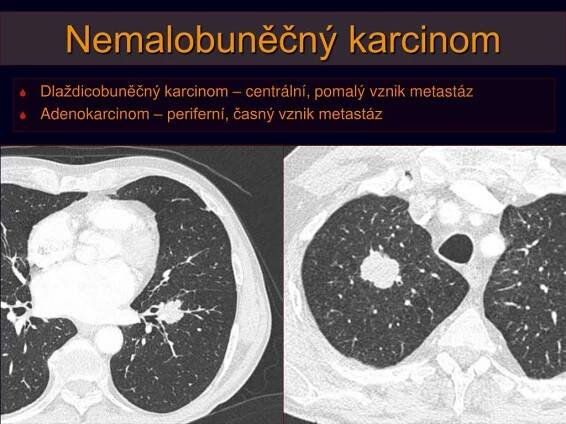

PPT - Nádory plic, pleury a mediastina: BRONCHOGENNÍ KARCINOM PowerPoint Presentation - ID:5892677

slideserve.com